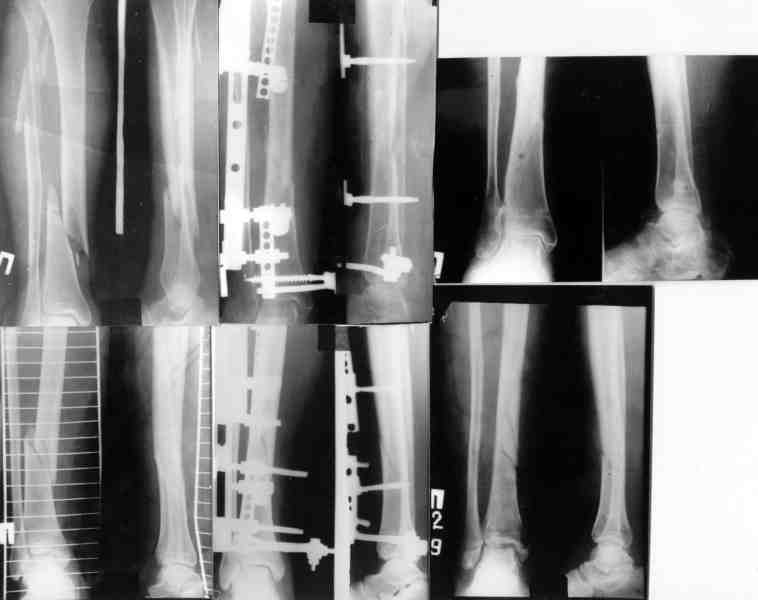

ММВ> выполнен закрытый блокируемый остеосинтез. Клинически результатом

ММВ> доволен. Рентгенологически - не вполне. нужно было погрузить стержень

В целом можно поздравить, очень неплохо. Рассверливали ли канал? Вверху вроде один винт, и в динамическом отверстии - лучше бы в статическое, а то стержень можт еще вылезти. А что за стерюень? Похоже на ChM. Из-за того, что выстоит, либо придется удалять рано или поздно. Либо через 2-3 мес. сделать ревизию - извлечь фиксатор, канал немного углубить и рассверлить, и тот же стержень ввести уже поглубже.

В дистальном отделе хватит и одного винта, лучше переднезаднего, чтобы поберечь лучевой нерв.

Канал не рассверливал. Стержень 7мм.ChM. В статическое отверстие не стал вводить винт, побоялся попасть в пустоту, а зря. Лучевой нерв видел,когда вводил дистальные винты. Антибиотики сменены, но складывается впечатление, что они не нужны.